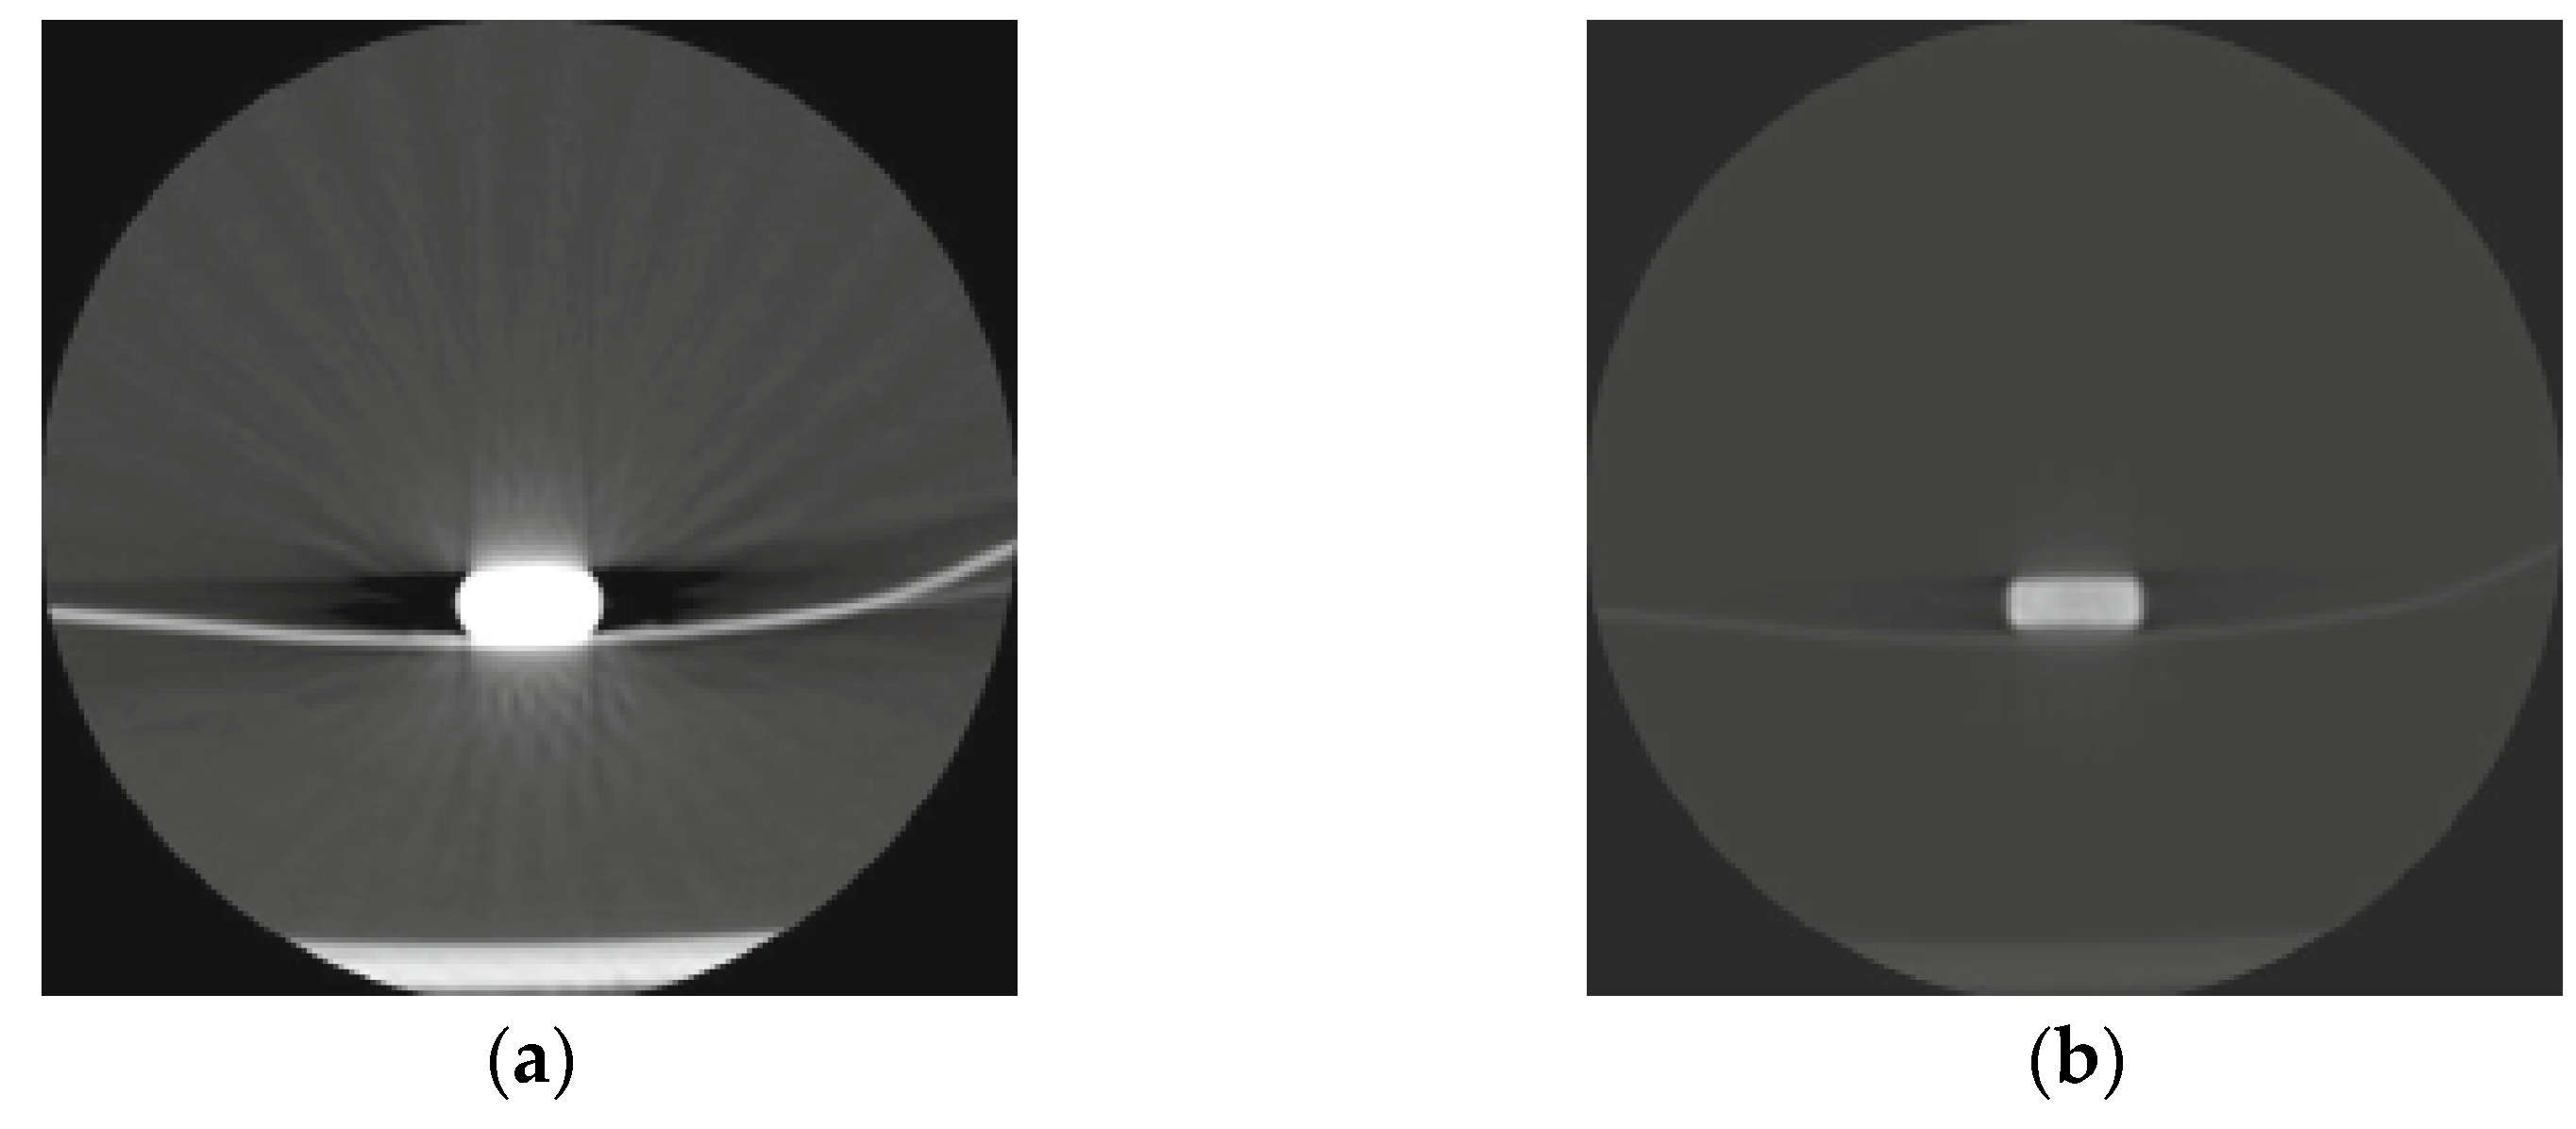

- Hayashi, H.; Machida, M.; Sekine, T.; Yamaguchi, H.; Kiriyama, T.; Kumita, S. Beam-hardening artifacts on computed tomography images caused by lanthanum carbonate hydrate in a patient on dialysis. Jpn J. Radiol. 2010, 28, 322–324. [Google Scholar] [CrossRef] [PubMed]

| Hayashi et al. | 2010 | CT | Multiple, hyperdense elements with sharp edges + beam hardening. | Intestines | Foreign bodies | Radiologists should be familiar with the appearance of LC. Temporarily switch to a different phosphate binder before the radiological examination. If CT or X-ray is necessary, perform before administration of LC. | Beam-hardening artifacts on computed tomography images caused by lanthanum carbonate hydrate in a patient on dialysis SpringerLink |